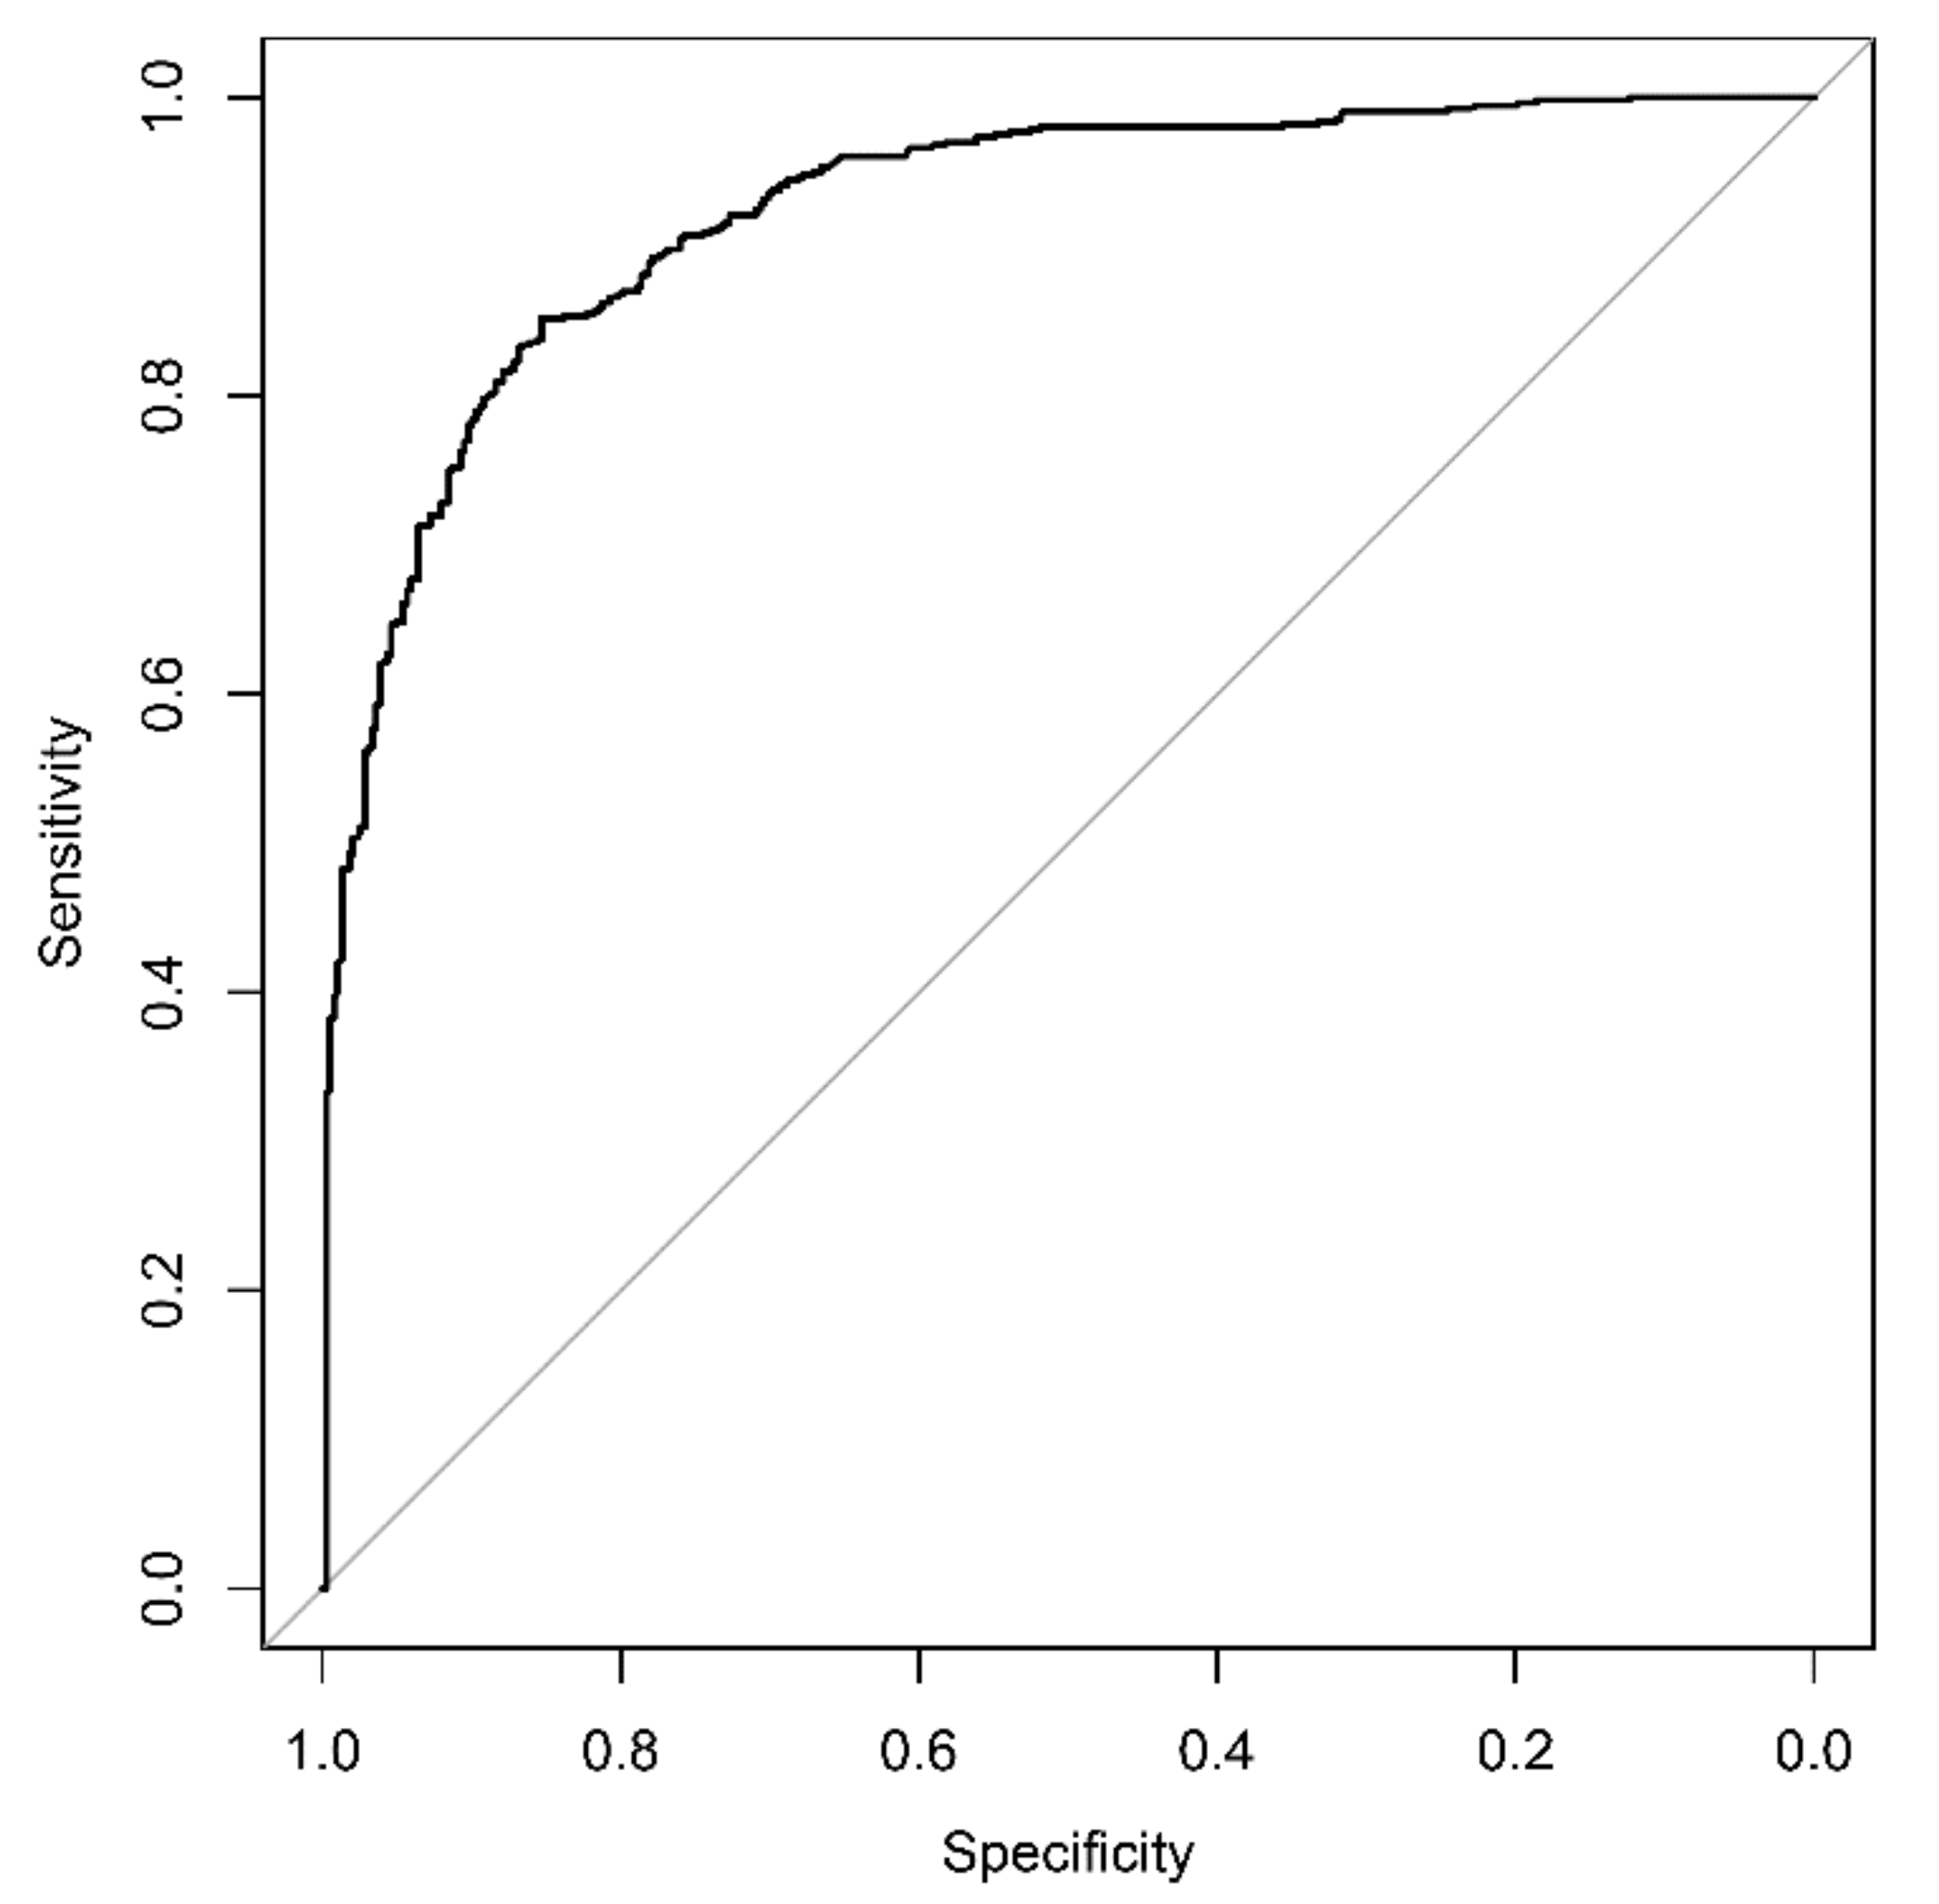

3.3. AI-Based Diagnostic Performance